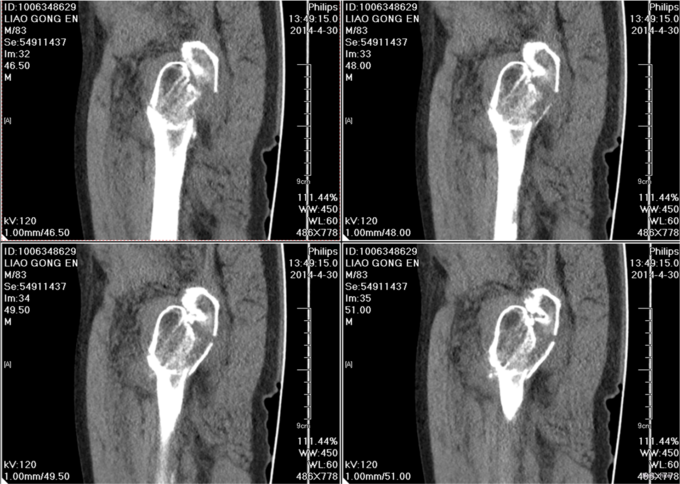

入院后完善检查,查无手术禁忌症后行左股骨粗隆间骨折闭合复位内固定术。患者术后第二天下地行走,术后3天自动退院。

患者早期手术治疗后,可以早期下地,防止骨科并发症的发生,提高患者生命质量。